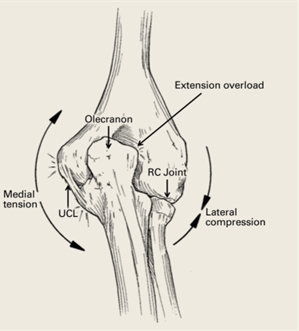

Valgus Extension Overload

- Valgus extension overload is a condition characterized by posteromedial elbow pain related to repetitive microtrauma in throwing athletes

- Repetitive stress through the throwing motion leads to excessive shear forces on the medial aspect of the olecranon tip/olecranon fossa and lateral compressive forces which can lead to:

- Cartilage loss across the olecranon or olecranon fossa

- Osteochondral lesions of the capitellum

- Posteromedial osteophytes with loose bodies

- UCL attenuation